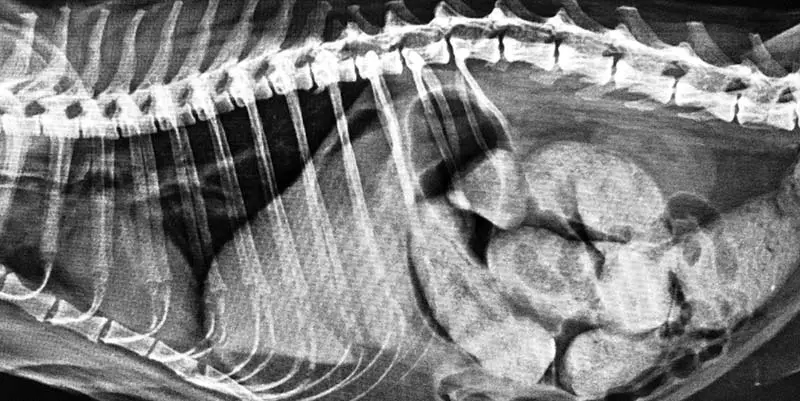

RADIOGRAM 1. Radiogram osłabionego osobnika żako (Psittacus erithacus) wykonany bez znieczulenia, w kartonowym pojemniku. Uwidacznia się na nim stare złamanie trzonu prawej kości ramiennej. Rozróżnić można na nim bezcieniowe pola worków powietrznych brzusznych oraz piersiowych doogonowych. Szczegółowa ocena narządów jamy ciała jest utrudniona (Fot. 1).

Fot. 1 Radiogram osłabionego osobnika żako (Psittacus erithacus) wykonany bez znieczulenia w kartonowym pojemniku